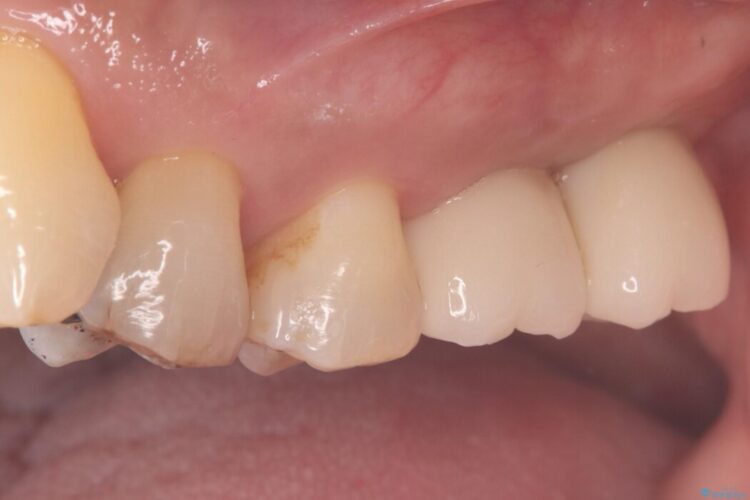

左上奥歯の欠損を、抜歯即時埋入を活用したインプラントで修復しました。

精密な位置決めと効率的な術式により、短期間でしっかり噛める喜びとお口全体の健康なバランスを取り戻すことができました。